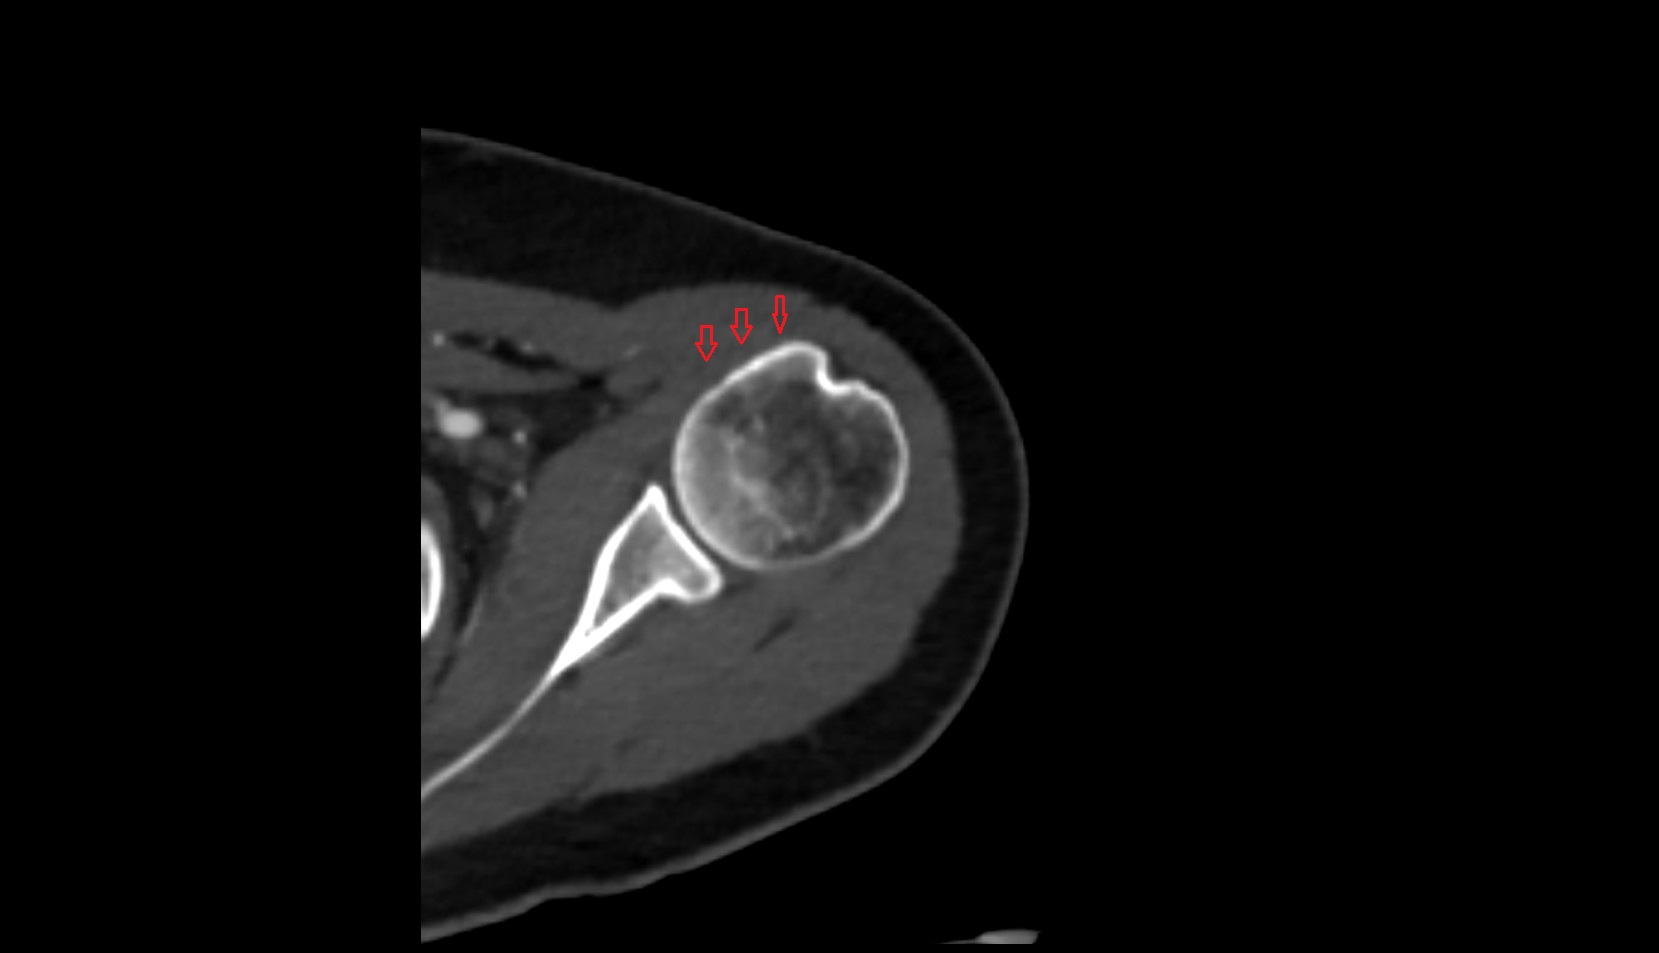

- Shoulder joint (glenohumeral joint)